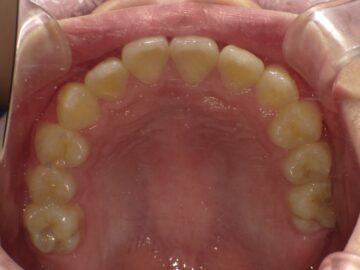

上顎の骨には繋ぎ目が存在しており、そこで左右二つの骨に分かれています。急速拡大装置を上顎に固定して装置の中央にあるネジを回すことで繋ぎ目を広げ、徐々に上顎の骨の変えていきます。そうすることで、顎の骨が正しい形に成長していくよう促され、永久歯を正しい位置で生えるように誘導できます。